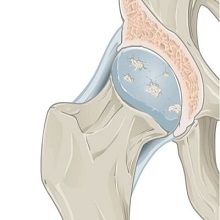

У нашој болници листе чекања су много краће него у појединим здравственим центрима где се чека и преко годину дана. У Oпштој болници Панчево на операцију кука чека се око 8 месеци, док пацијенти који оперишу катаракту на ову хирушку интервенцију чекају најдуже два месеца. |

| Једна од веома честих болести колена у општој популацији је остеоартритис. То је хронична болест дегенеративне природе тј. последица је измена у ткивима која сачињавају зглоб, а које настају процесом старења организма. Остеоартритис није специфичан за одређене зглобове, већ може захватити било који. Када је зглоб колена захваћен, то се назива гонартроза. |